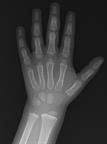

X-Rays in Teens: What to Expect

An X-ray showing the lower arm, wrist, and hand.

X-rays are pictures of the inside of your body. An X-ray machine makes these pictures using waves of energy known as radiation. Your health care provider may use X-rays to look for problems like broken bones, joint problems, lung infections, and causes of stomach pain.